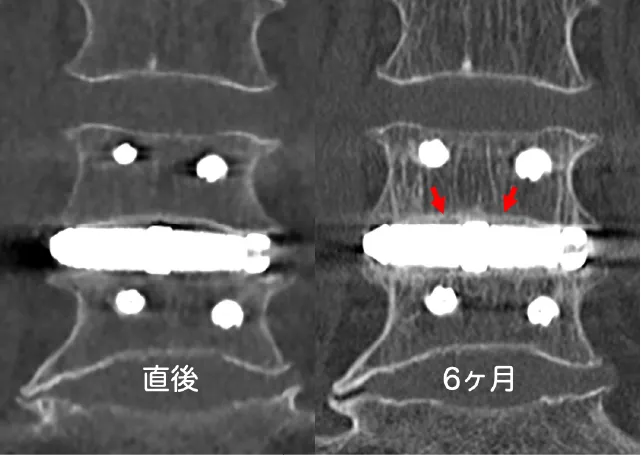

2018年に薬事承認を取得した低侵襲腰椎側方固定用の人工骨です。自家骨を採取せずに手術が可能になったため、低侵襲の手術が可能になりました。すでに日本全国で多くの患者さまの治療に用いられています。

低侵襲腰椎側方固定用人工骨:X-TAL

-

骨と人工骨の結合